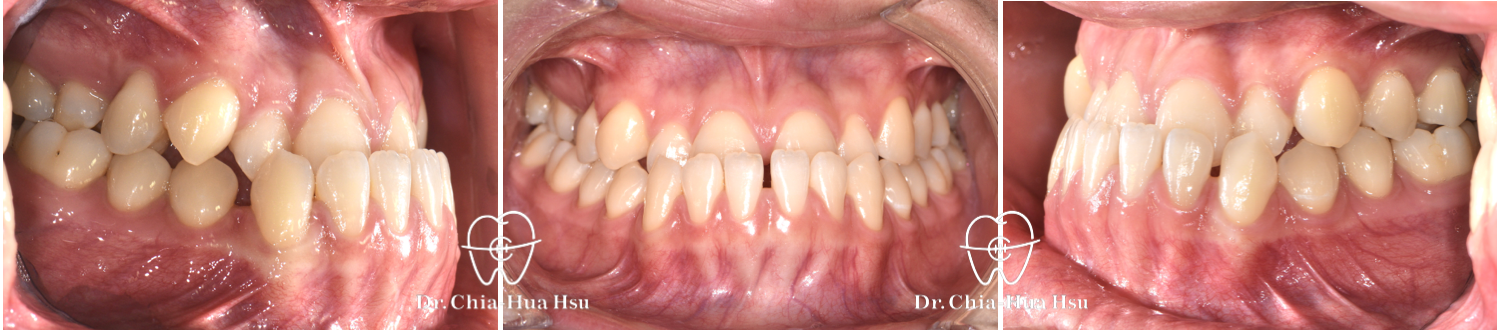

治療前

治療後

• 問題分析:患者是標準的骨骼三類咬合(Skeletal Class III),下巴明顯較長,還有上顎牙弓過窄、開咬以及齒列不正。

• 治療方式:使用傳統金屬矯正器,合併正顎手術(雙顎),上顎拔除兩顆小臼齒以利手術方式進行上顎牙弓擴寬。

• 治療結果:齒列排齊,咬合功能恢復,外觀更和諧。